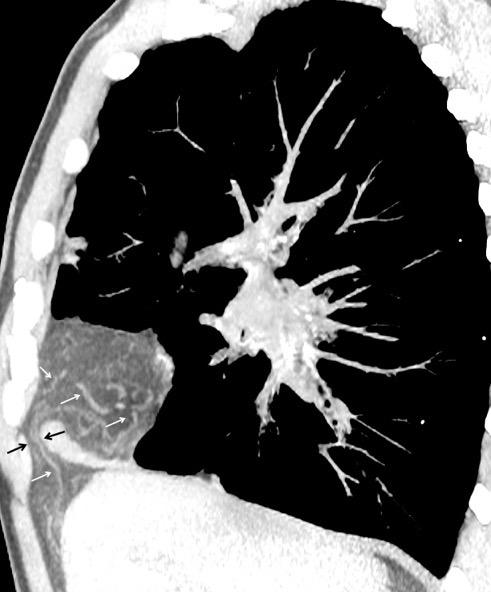

30 años

Borramiento de la banda PARA-aórtica por AdenoCa. de LII, no visible en 2005

Colapso de LII. TC: secreciones bronquiales.

Endoscopia tapón mucopurulento extraído

Borramiento parcial por Ca. epidermoide.